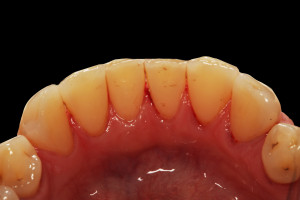

Do kliniki Stomatologia Bez Bólu zgłosiła się pacjentka, lat 61 z problemem nadwrażliwości zębów. Po przeprowadzonym wywiadzie stwierdzono spożywanie sporej ilości sezonowych owoców (truskawki, wiśnie, czereśnie, czarna porzeczka), nawet 3 razy dziennie. Następnie wykonano badanie wewnątrzustne. Stwierdzono obecność płytki nazębnej, ciemnego osadu oraz kamienia nazębnego na części trzonowców:

Wykonano higienizację jamy ustnej poprzez usunięcie kamienia nazębnego skalerem ultradżwiękowym, zdjęciem osadu i płytki nazębnej poprzez piaskowanie air flow plus oraz classic, a następnie wypolerowaniu gumką ze specjalistyczną pastą polerską: